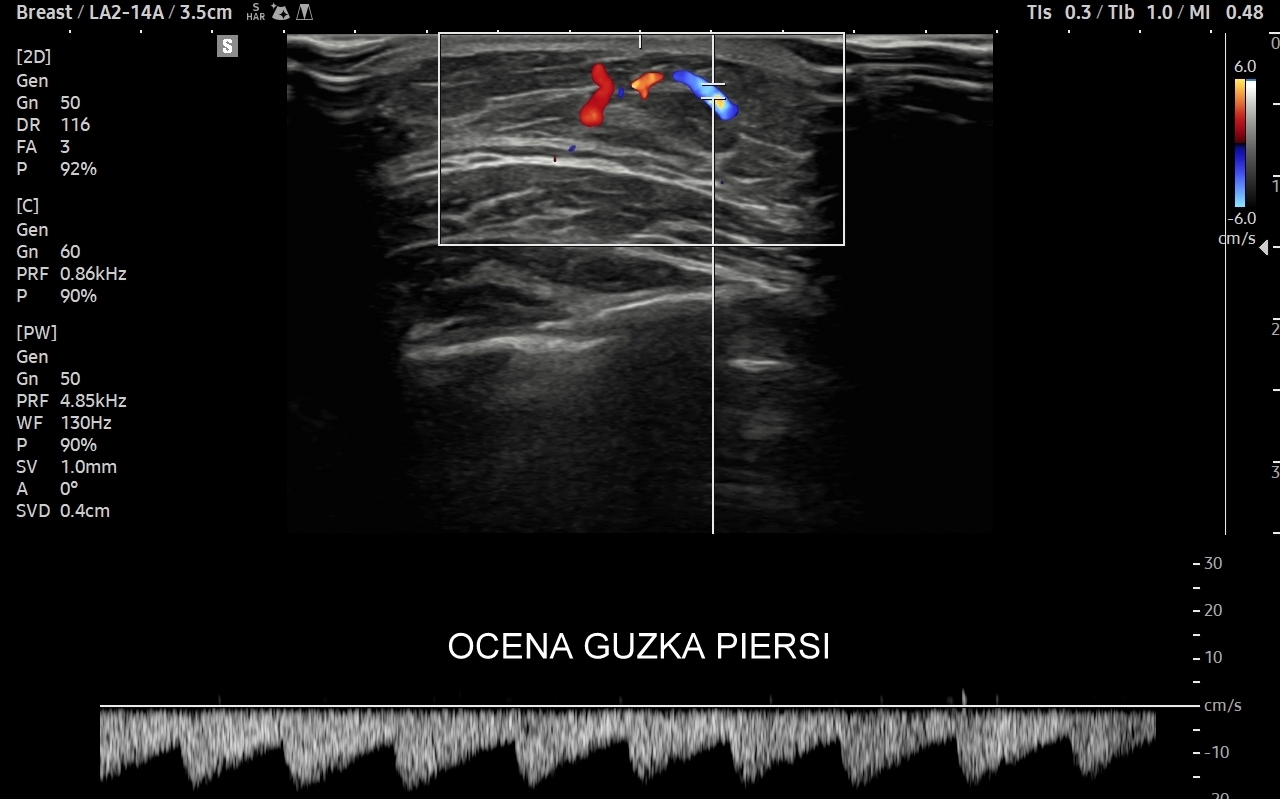

USG piersi z kontrastem CEUS

Badanie USG piersi z kontrastem (CEUS) jest najnowszą metodą diagnostyczną piersi i rozwinięciem badania multiparametrycznego USG (MPUS). Główną rolą badania CEUS piersi jest zwiększenie precyzji oceny guzków piersi pod kątem kwalifikacji w skali BIRADS, a przez to uniknięcie niepotrzebnych biopsji piersi. W przeciwieństwie do innych metod diagnostycznych zasadniczą zaletą badania CEUS jest możliwość jednoznacznego wykazania lub wykluczenia unaczynienia guzka piersi. Podejrzany guzek, którego unaczynienia lub cech nie można jednoznacznie ocenić w standardowym badaniu USG można poddać badaniu USG z kontrastem. Otóż w przypadku, gdy zmiana nie posiada unaczynienia to nie jest ona nowotworem. Niezależnie od kwalifikacji guzków łagodnych badanie CEUS ma możliwość w wielu wypadkach uwidocznienia ukrytych dodatkowych cech świadczących o złośliwości guzka.

Badanie CEUS jest bezpieczne dla organizmu i nie obciąża nerek, w przeciwieństwie do kontrastu przy tomografii komputerowej czy rezonansie magnetycznym. Pierwszym lekarzem w Polsce, który ambulatoryjnie zastosował metodę CEUS piersi jest dr Tomasz Szczepański; badanie odbyło się w 2024 r. we Wrocławiu w Opiece Medycznej Golden Care.